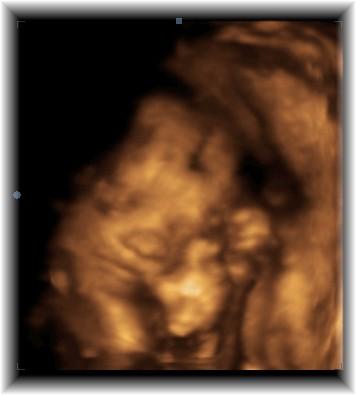

nochmal eins

Bild zu

Ach goooooott - ist das niedlich :) Gähnt es da grade? Hihi, ich freu' mich, dass Du jetzt eine so schöne Erinnerung an dieses Stadium der SS hast! LG, Tiffy

Oh mein Gott!!! Ist das niedlich!!! Das sind wirklich schöne Bilder? In welcher Woche bist du denn jetzt? Lg Karina

25 ssw haben es dreimal versucht und heute ging es endlich und dankeschön für die lieben komplimente